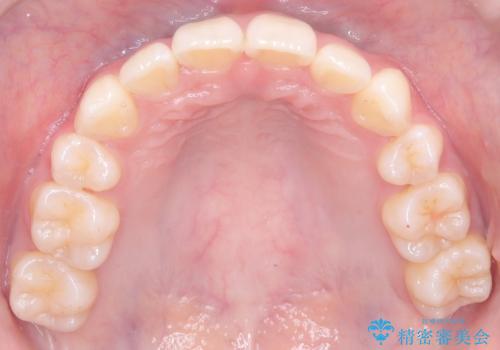

- 前歯が突き出ていることによる口元の突出感と、下顎が右側にズレていること(右方偏位)を主訴にご来院されました。

精密検査の結果、歯を並べるスペースの不足に加え、上下の歯列の正中(中心)が大きくズレていることが確認されました。突出した口元を下げ、顎の左右バランスを整えるためのスペースを確保するため、右上・左上・左下の4番目(第一小臼歯)を計3本抜歯する計画を立案。装置は、治療中の見た目にも配慮し、目立ちにくい審美ワイヤーを選択しました。

治療は、抜歯によって得られたスペースを活用し、前歯を後方へ移動させながら上下の中心を一致させる緻密な調整を行いました。